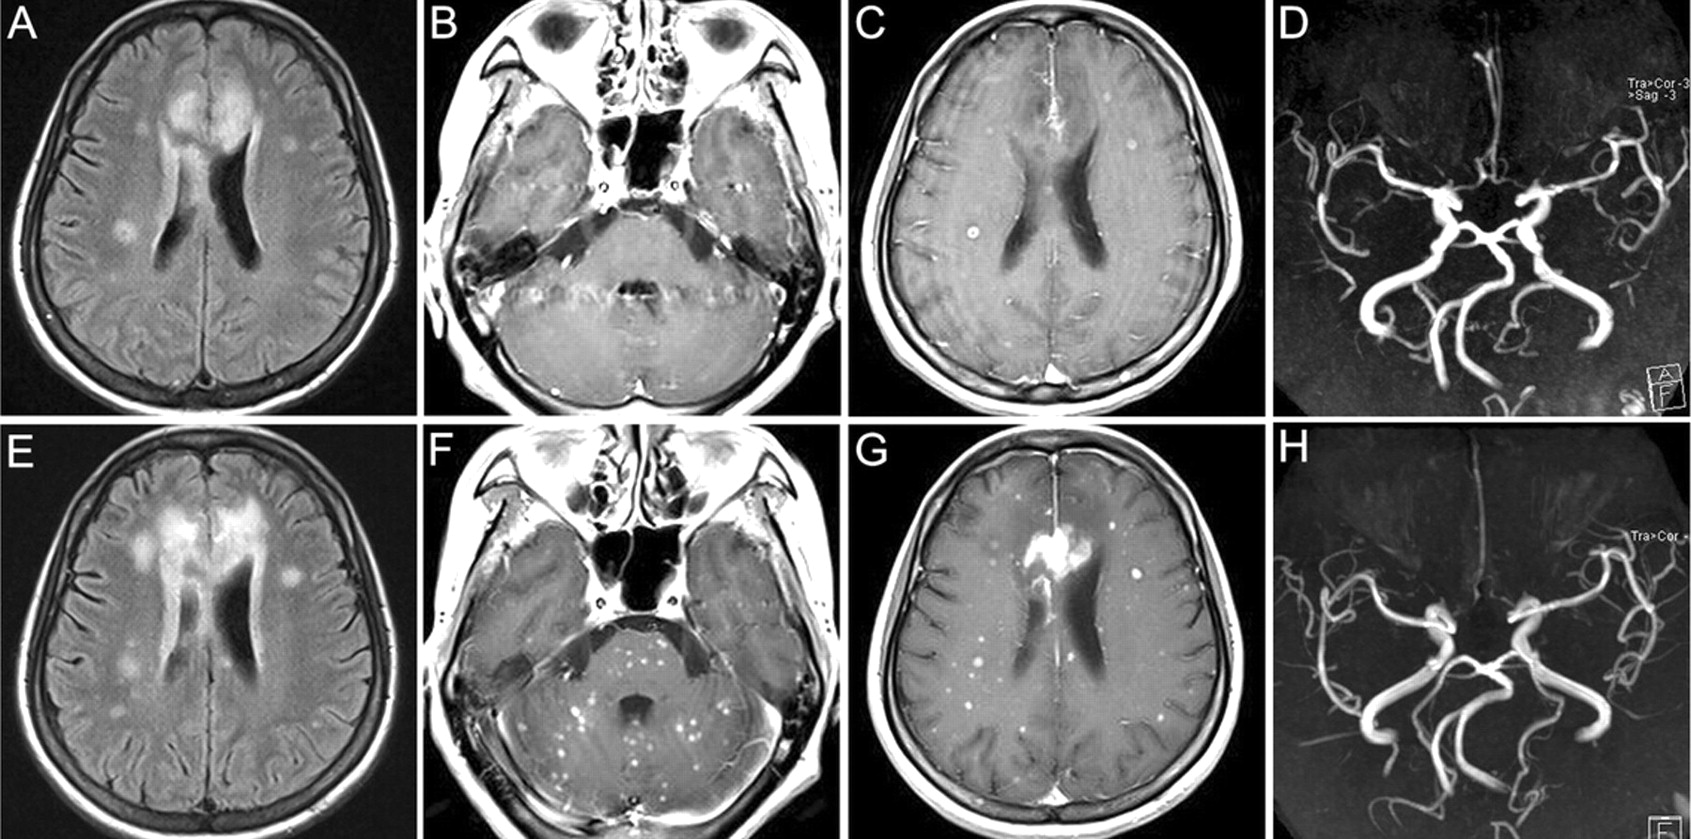

图初始和后续的MRI检查

初始MRI显示急性梗死的扣带皮层和胼胝体天赋序列(A)和小脑和大脑中的几个钆增强结节样病变(B和C)。先生前脑动脉血管摄影显示轻度狭窄的近端(D)。随访MRI表现40天后显示略有显著增加梗死(E)的大小和数量的增加提高整个大脑病变血管造影术显示先生(F和G)。严重的弥漫性狭窄的大脑前动脉(H)。